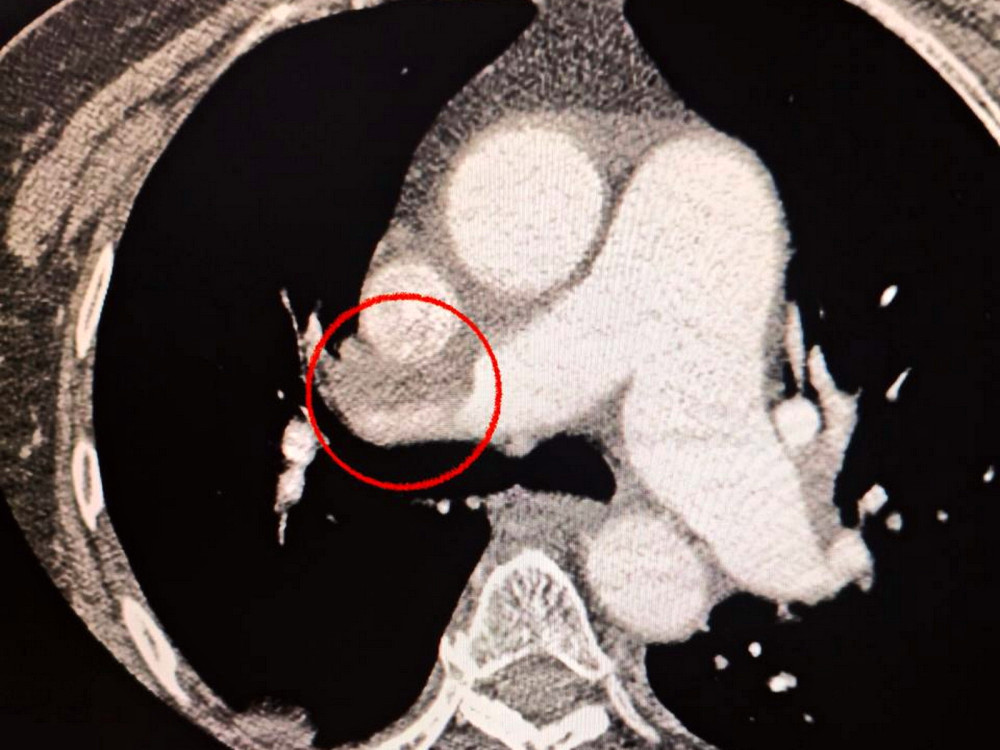

The patient was admitted to the hospital with a severe stroke. During a CT scan, doctors discovered a blockage in the middle cerebral artery.

Additionally, the medical team noted that the patient was having difficulty breathing, prompting further lung examinations that confirmed the presence of pulmonary embolism.